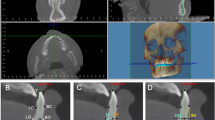

Positional assessments of the condylar. A Measurements of the anteroposterior relationship and lateromedial displacement of the condylar. GC, the geometric center of the condyle; a, the anteroposterior distance difference between GC of the right and left condyle to the MSP; b, the long axis of the condylar process; c, the distance between CG of the right and left condyle to the MSP; θ, the angle between the long axis of the condylar process and the MSP. B Measurements of the vertical relationship of the condylar. d, the vertical distance difference between GC of the right and left condyle to the MSP

Condylar analysis

The geometric center (GC) of the condyles was first identified on the axial view. Then, the anteroposterior [20] (Fig. 2A) and vertical [21] (Fig. 2B) relationship of the condylar was measured by calculating the distance difference between the GC of the right and left condyle to the MSP. The right or the crossbite side of the condyle was considered as 0 point [20]. A positive value indicates that the left or the non-crossbite side of the condyle was positioned anterior or higher to the 0 point, and a negative value indicates a posterior or lower position. The transverse position of the condylar was measured by calculating the distance between the GC of the condylar and MSP. The lateromedial displacement of the condyle was assessed by measuring the angle between the long axis of the condylar process and the MSP (Fig. 2A).